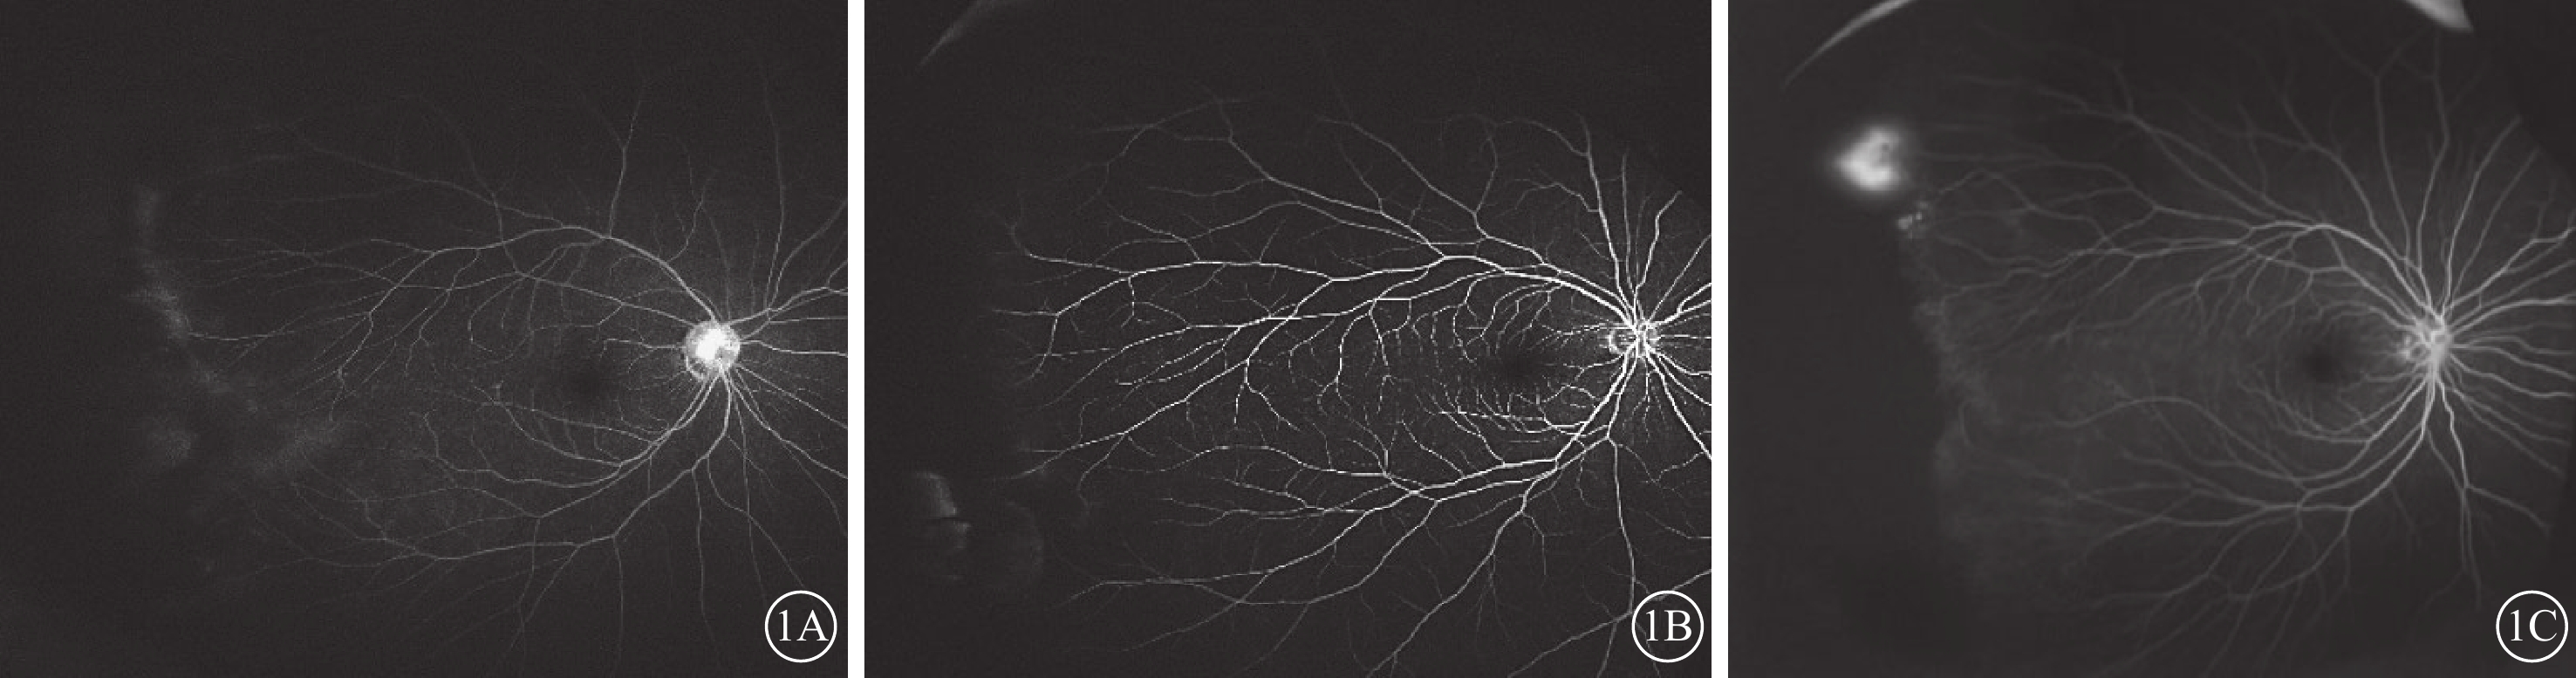

同一家系中同一基因突變者其眼底表現不同。家系1先證者父母親及姐姐均攜帶LRP5基因突變,父親雙眼顳側周邊視網膜血管滲漏,右眼周邊無血管區(圖1A);母親右眼顳側周邊無血管區,末端血管呈“毛刷狀”,伴少許熒光素滲漏(圖1B);姐姐雙眼顳側周邊無血管區,右眼顳上方周邊新生血管團熒光素滲漏(圖1C)。家系39先證者及其一級親屬未檢測出FEVR相關致病性基因;其父親FFA檢查,雙眼顳側周邊視網膜血管分支增多、變直,異常血管襻(圖2)。未攜帶FEVR相關致病基因的13個家系的一級親屬中,眼底表現為FEVR相關視網膜血管特征性改變3個家系。